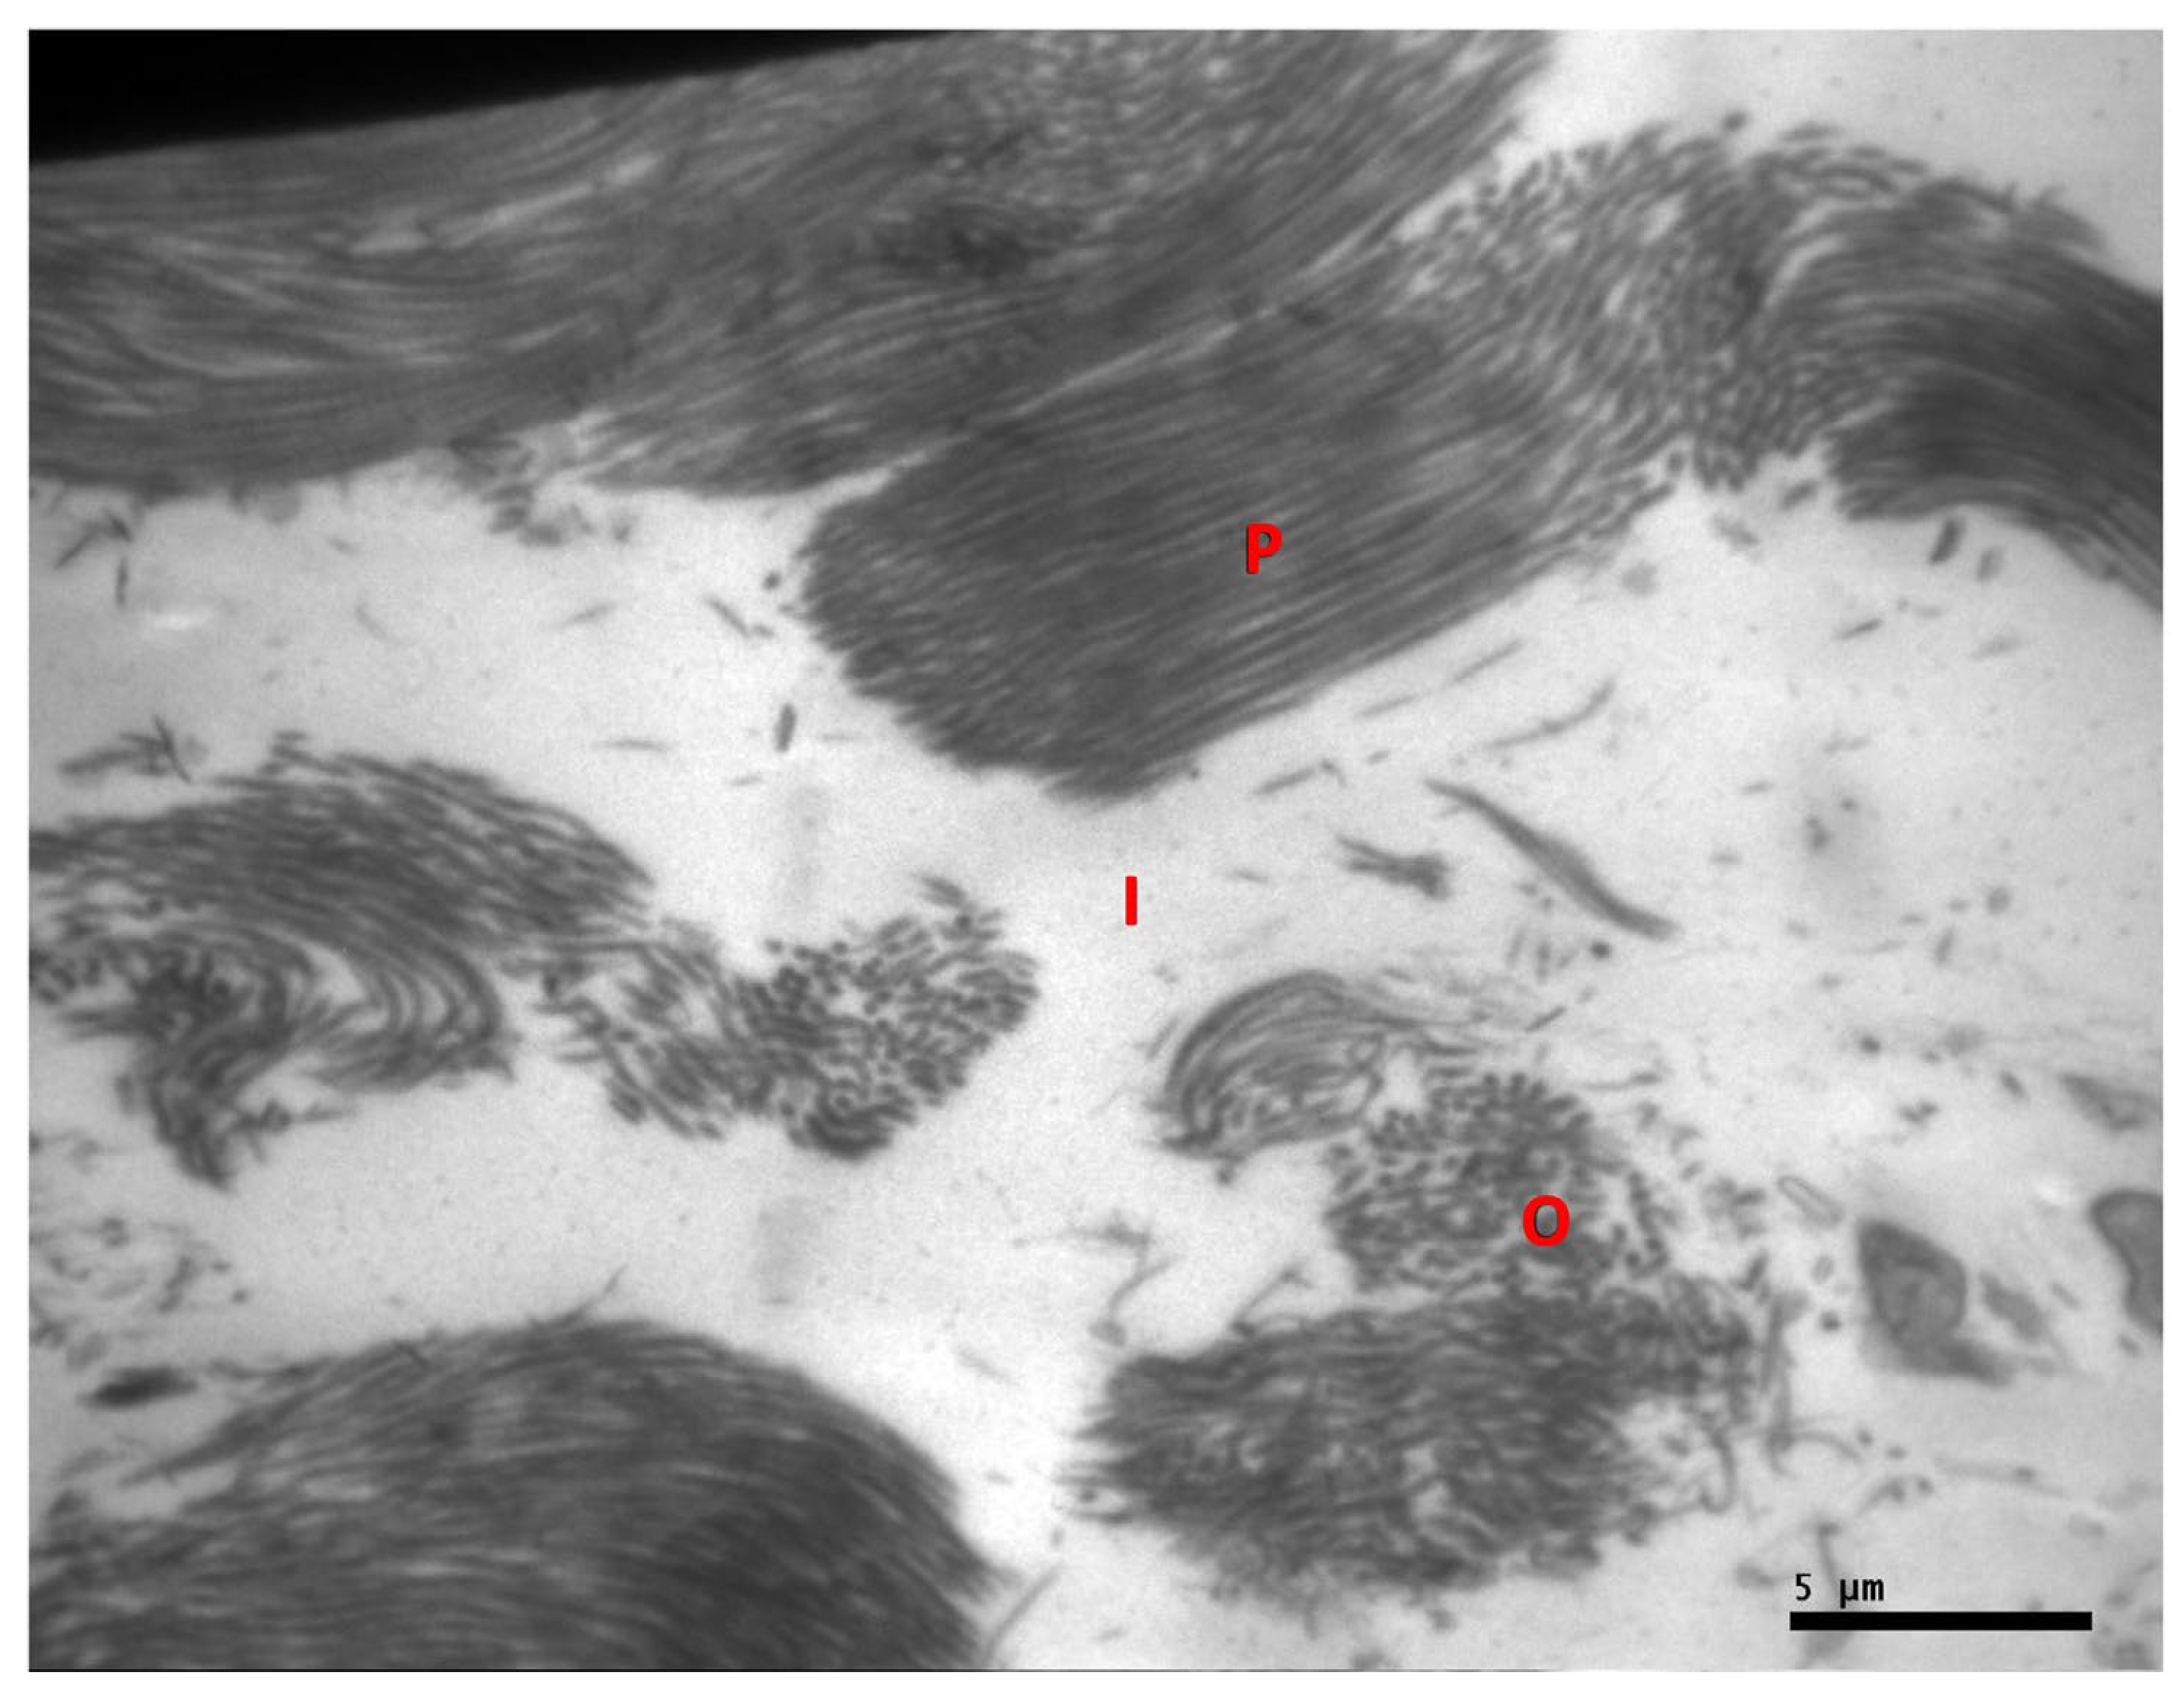

2.3. Electron Microscopy Evaluation

3.8. Assessment of Tendon Sample